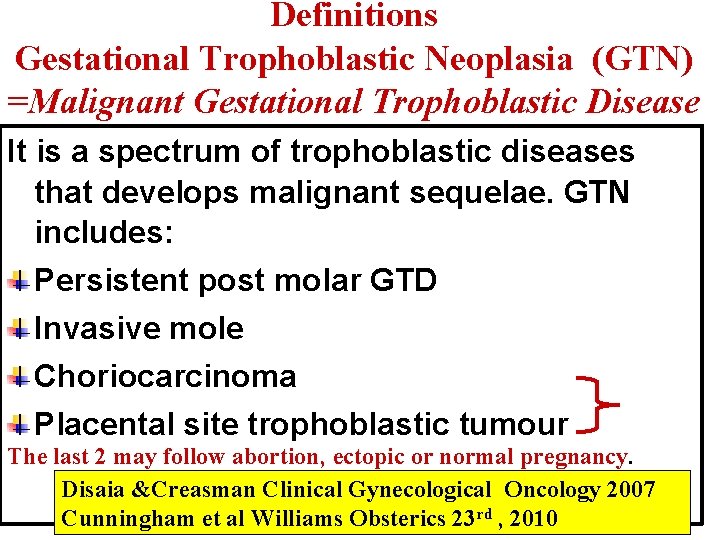

Definitions Gestational Trophoblastic Neoplasia (GTN) =Malignant Gestational Trophoblastic Disease It is a spectrum of trophoblastic diseases that develops malignant sequelae. GTN includes: Persistent post molar GTD Invasive mole Choriocarcinoma Placental site trophoblastic tumour The last 2 may follow abortion, ectopic or normal pregnancy. Disaia &Creasman Clinical Gynecological Oncology 2007 Cunningham et al Williams Obsterics 23 rd , 2010